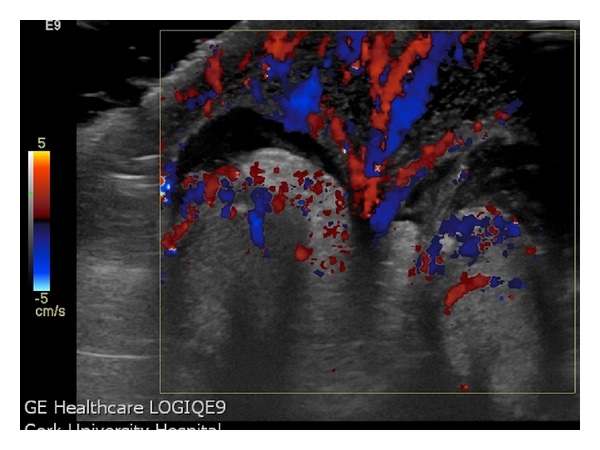

Manuel � un ragazzino di otto anni, che viene portato in Pronto Soccorso per la comparsa da alcune ore di una tumefazione scrotale, accompagnata da una vaga dolenzia localizzata. Non � presente una storia di traumi, febbre o disuria. Obiettivamente lo scroto si presenta iperemico e tumefatto bilateralmente, anche se in maniera asimmetrica, senza interessamento del pene, dell'inguine o del perineo (Figura 1). I testicoli sono palpabili ma tale manovra provoca un vivo dolore; i riflessi cremasterici non sono evocabili e la transilluminazione scrotale risulta negativa. Figura 1. Scroto iperemico e tumefatto, in caso di edema scrotale. Figura 2. Ecografia scrotale: importante ispessimento del tessuto cutaneo-sottocutaneo. Figura 3. Ecografia color-doppler del paziente. Figura 4. Ecografia color-doppler che mostra il �segno della fontana� dato dall�aumento del flusso sanguigno nella pelle scrotale edematosa (da voce bibliografica 1).

Un'ecografia scrotale (Figura 2), richiesta in urgenza per escludere una possibile torsione, ha mostrato entrambi i testicoli in posizione pi� alta che di norma, con volume regolare e vascolarizzazione conservata, senza lesioni focali. Il reperto dirimente � stato per� il riscontro di un importante ispessimento del tessuto cutaneo-sottocutaneo scrotale, con intensa iperemia nella valutazione con il color-doppler che nelle sezioni trasverse disegnava l'immagine di una �fontana scrotale� (Figure 3 e 4), suggestiva di Edema Scrotale Acuto Idiopatico (AISE). La negativit� degli indici di flogosi ha escluso con certezza che potesse trattarsi di una cellulite in fase iniziale.

L'AISE � una condizione benigna, una dermatosi, a cui fa capo, secondo la letteratura, dal 3% al 20% di tutti i casi di scroto acuto. Si tratta di una diagnosi di esclusione di altre patologie per cui un intervento si rende immediato, prima fra tutte la torsione testicolare. L'ecografia � l'ausilio diagnostico pi� importante a tale scopo e la valutazione con color-doppler pu� evidenziare il �segno della fontana�, immagine caratteristica data dall'incrementato flusso sanguigno all'interno dei tessuti molli peritesticolari.